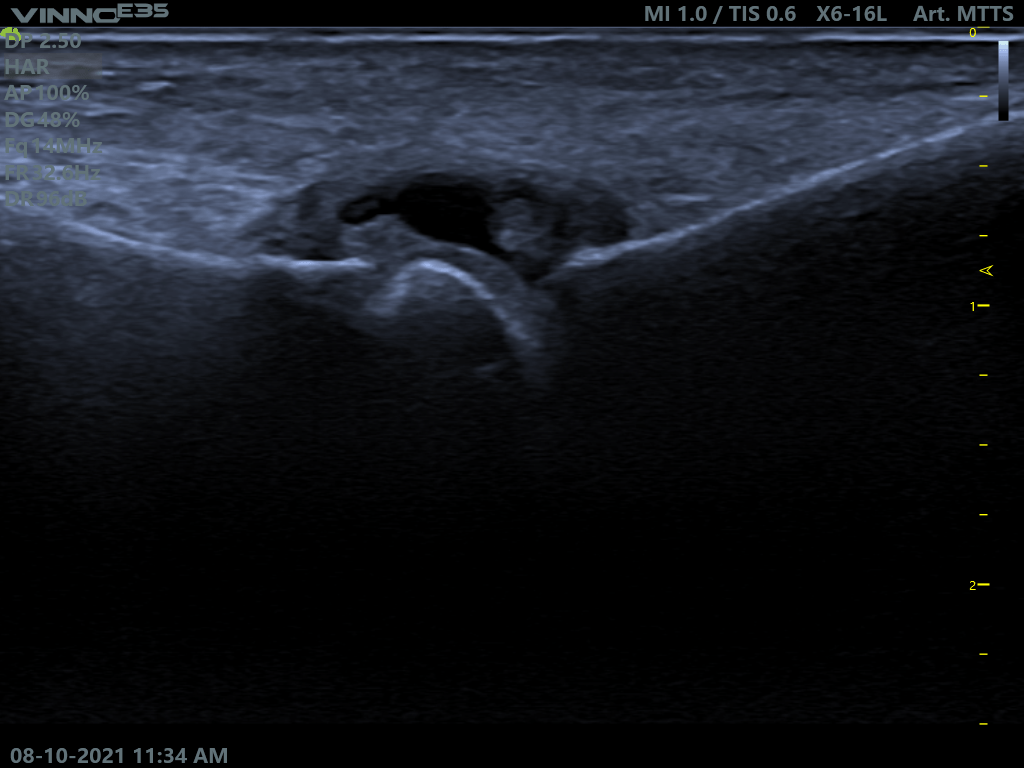

La infiltración ecoguiada es una técnica para tratar la patología articular, muscular, ligamentosa, del tendón y de la fascia mediante la introducción de sustancias medicamentosas con ayuda de un ecógrafo en tiempo real, con una precisión de practicamente en 100%, en el tejido o estructura lesionada. Gracias al uso del ecógrafo en las infiltraciones podemos acceder a la zona lesionada sin dañar otras estructuras durante el recorrido de la aguja y maximizar la acción farmaceutica, ya que el medicamento va solo a la zona dañada, lo que aumenta la probabilidad de éxito del tratamiento.

Por lo tanto, ayudará a aliviar el dolor, reducir la inflamación o mejorar la movilidad en enfermedades como artritis, tendinitis, fasciopatias o bursistis.

Casos prácticos